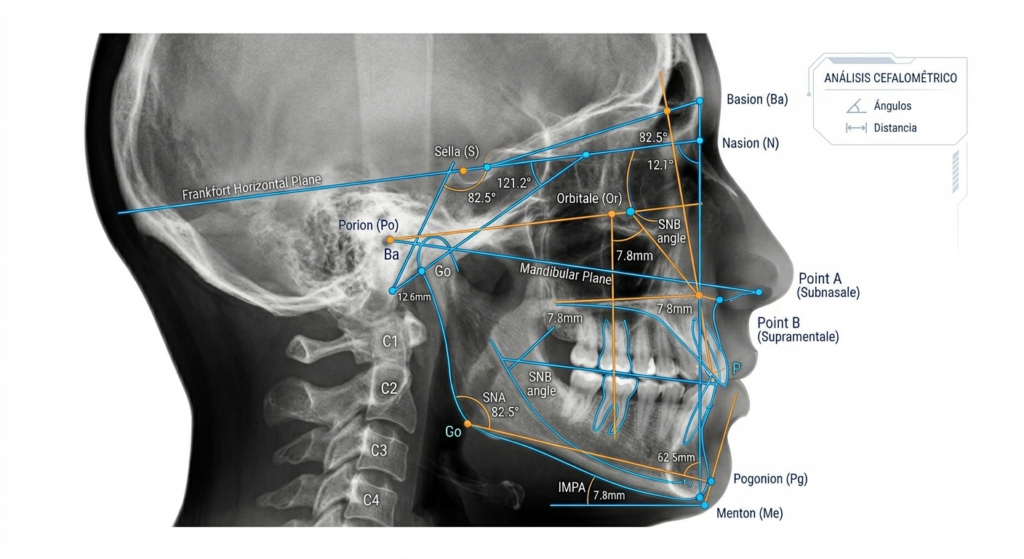

Diagnóstico Cefalométrico

Análisis profundo de huesos y tejidos para un diagnóstico técnico que garantice la precisión de tus resultados finales.